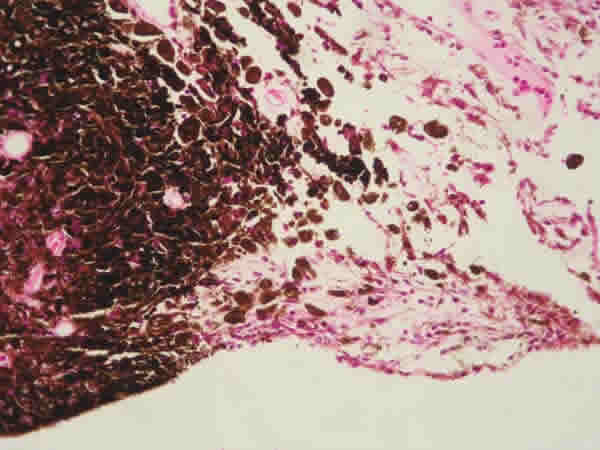

El informe de anatomía patológica describía la lesión como nodular, perfectamente delimitada y simétrica, ocupando todo el espesor del iris, cuyas células formaban una población uniforme, con citoplasma altamente pigmentado, poligonales, con una alta proporción citoplasma/núcleo y sin hallazgo de atipias ni mitosis, llegándose al diagnóstico histopatológico de melanocitoma de iris (figs. 2, 3 y 4).

Fig. 2.